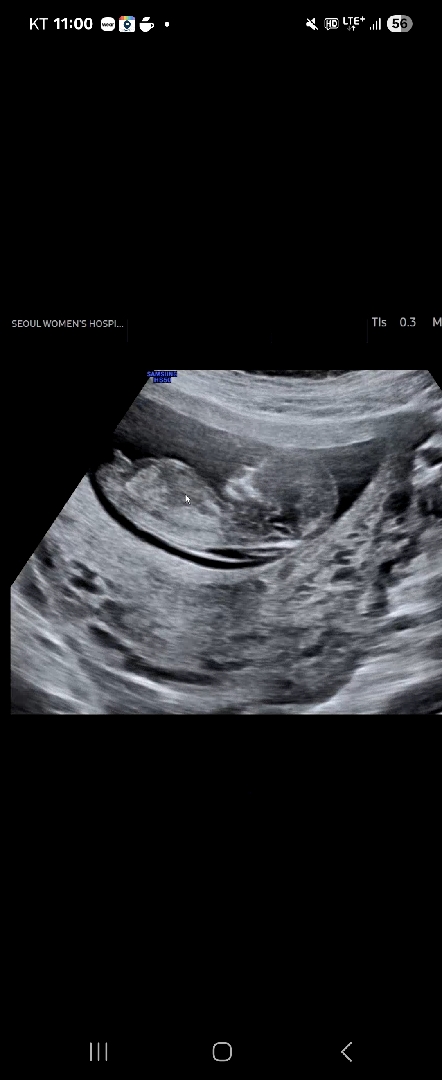

12주 1일 각도법 고수분들 한번 봐주세요!

첫찌 딸이라 둘째 성별이 너무 궁금한데 봐도봐도 어려워서 한번 봐주세요~